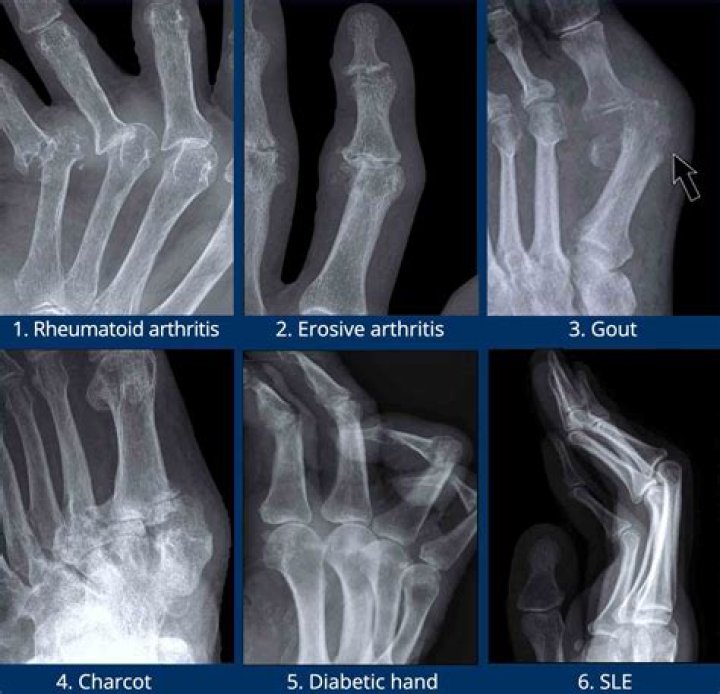

Misdiagnosis of Rheumatoid Arthritis Is Common. Many rheumatic diseases have overlapping symptoms, and that can complicate the effort to obtain an accurate diagnosis for RA. Some diseases are complex. They may have overlapping characteristics with other conditions, making diagnosis more difficult.